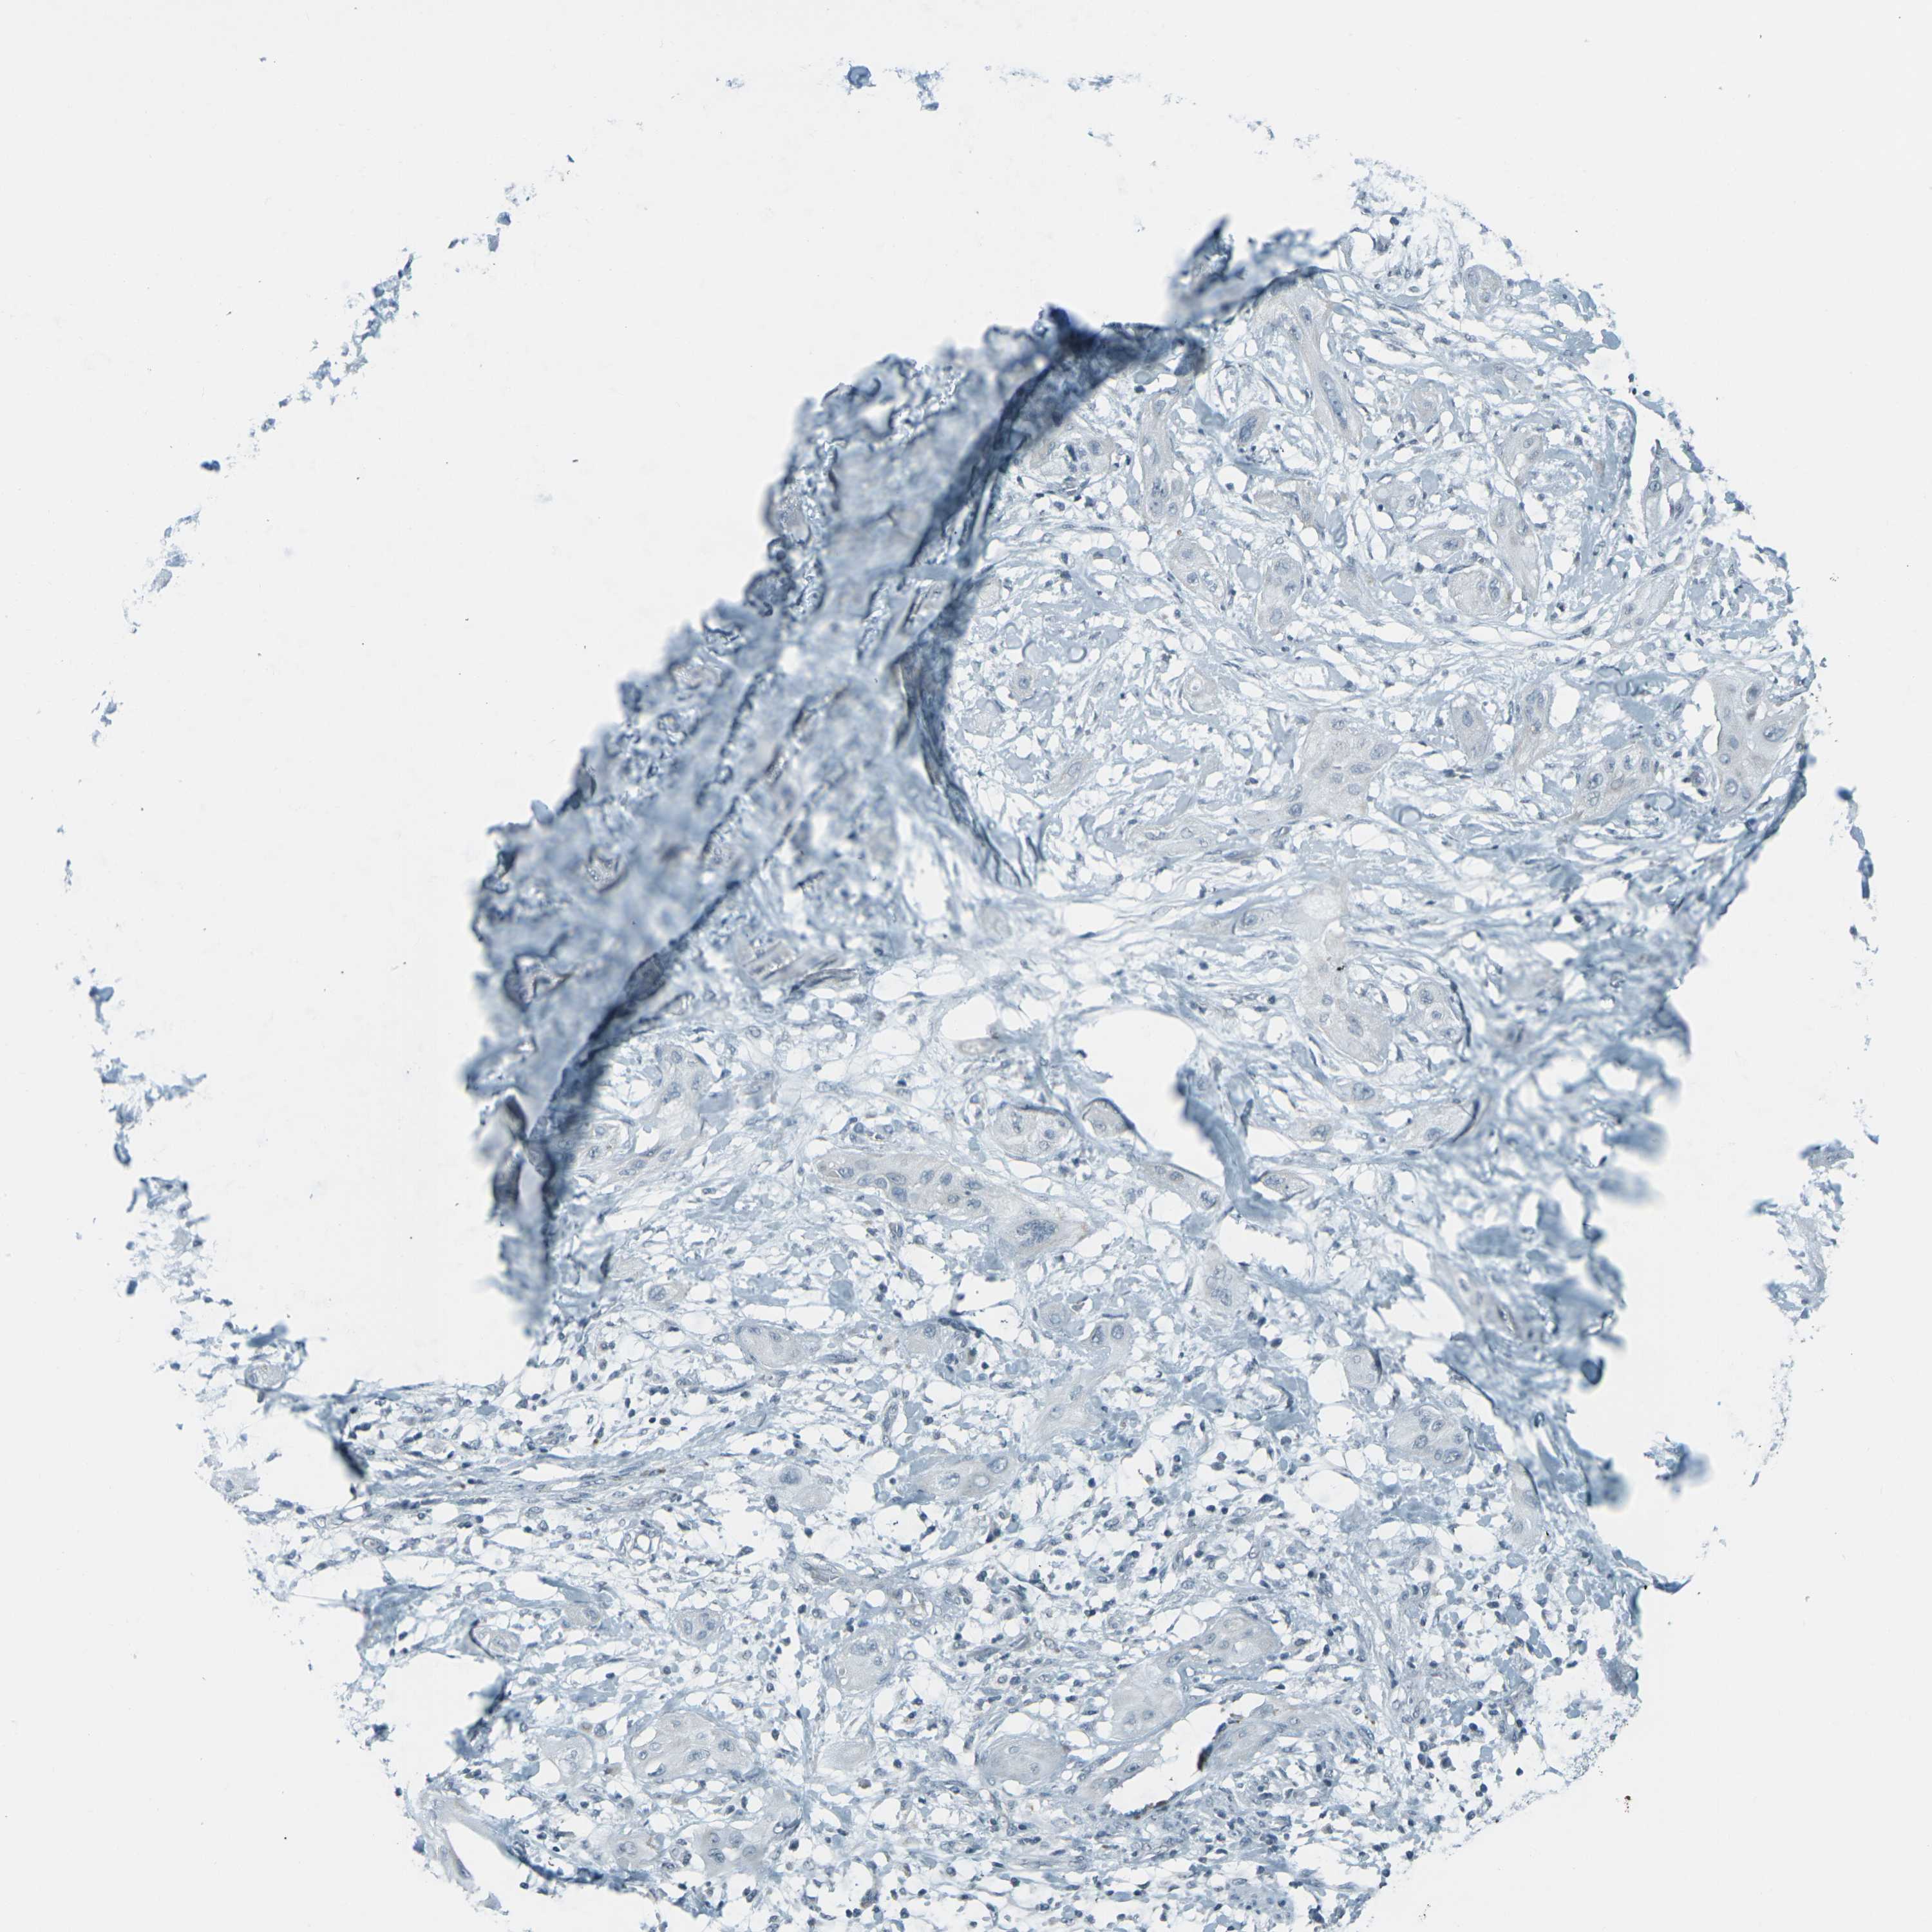

CANCER LUNG CANCER Show tissue menu

Lung cancer

Human cancer